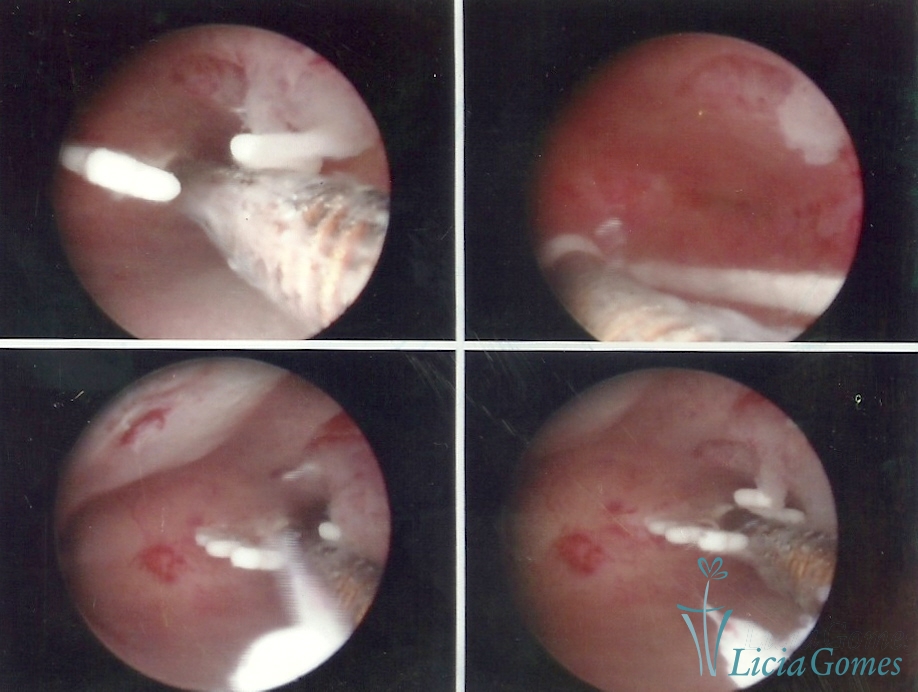

Canal cervical com fio do DIU